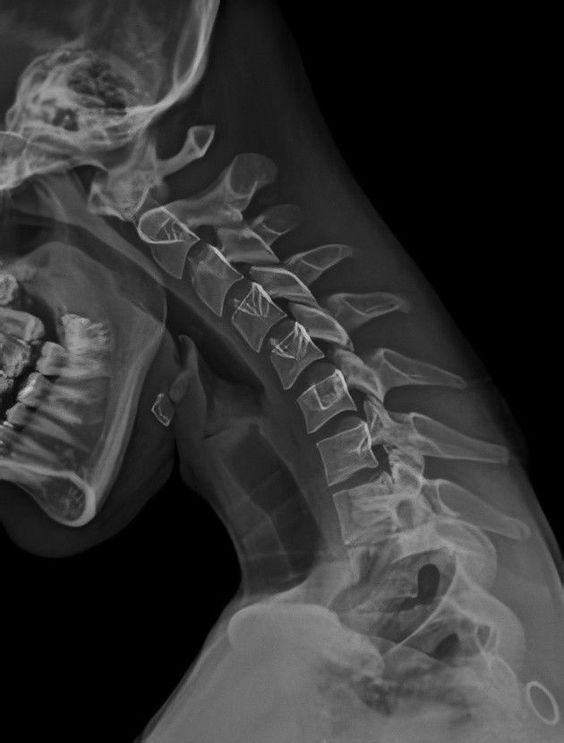

پرتوشناسی یا رادیولوژی (radiology) و گاهی تصویربرداری تشخیصی نام یک رشته از تخصصهای پزشکی است که از پرتو ایکس و دیگر اقسام امواج و پرتوها برای تشخیص و درمان بیماری و حالات غیر طبیعی کمک می گیرد. در تمام اینها، هدف تشخیص بیماری یا حالات غیر طبیعی بدن به کمک روشهای پیشرفته تصویری است.

رادیوگرافی برای نخستین بار در میدان جنگ برای تصویربرداری از بدن سربازان زخمی مورد استفاده قرار گرفت.

هشتم نوامبر، روز جهانی رادیولوژی است. در چنین روزی در سال ۱۸۹۵، ویلهلم کنراد رونتگن وجود اشعه اکس را کشف کرد. با مشاهده ساطع شدن نور از یک ورق فلورسنت (جسمی که بر اثر تابشی خاص، مانند اشعه اکس، از خود نور می‌دهد) که در نزدیکی یک لامپ اشعه کاتودی قرار گرفته بود، رونتگن برای اولین بار به وجود اشعه اکس پی برد. طی آزمایش‌های بعدی، او متوجه شد که اشیاء مختلف، اثر متفاوتی بر اشعه عبوری دارند. رونتگن با ثابت نگه‌داشتن دست همسرش در جلوی یک فیلم فلورسنت، اولین عکس رادیولوژی تاریخ را ثبت کرد.

اولین استفاده پزشکی از تصویر رادیولوژی توسط دکتر جان هال-ادواردز در سال ۱۸۹۶ انجام شد که ثبت عکس یک سوزن فرورفته در دست یکی از همکارانش بود. به دلیل اینکه مضرات اشعه اکس در ابتدا شناخته‌شده نبود، بسیاری از پزشکانی که با این روش تصویربرداری سر و کار داشتند دچار مشکلاتی مانند ریزش مو، مصمومیت پرتوی و سرطان شدند. برای مثال دکتر هال-ادواردز در سال ۱۹۰۸ به دلیل «سرطان پوست ایجاد شده بر اثر اشعه اکس»، دست چپش را از دست داد. مقالات او باعث شفاف‌سازی و حرکت به سوی ایمنی وسایل عکس‌برداری برای پزشکان و بیماران شد. در یک مطالعه منتشر شده در سال ۲۰۱۶، مشخص شد که رادیولوژیست‌ها در مقایسه با روان‌شناسان (که به هیچ وجه با دستگاه‌های پرتوزا سر و کار ندارند)، شانس برابری برای جان باختن به بیماری‌های ناشی از پرتوهای رادیواکتیو دارند.

امروزه انواع روش‌های تصویربرداری، روش‌های تشخیصی معمولی برای پزشکان هستند؛ برای مثال پزشکی ورزشی در سال‌های اخیر بسیار از روش‌های مختلف تصویربرداری استفاده کرده‌است. امسال روز جهانی رادیولوژی به نقش رادیولوژی در پزشکی ورزشی اختصاص دارد. در ورزشهایی مانند فوتبال، که دویدن، پریدن، تکل زدن و شروع به و توقف سریع از حرکت به کرات اتفاق می‌افتد، کشیدگی عضلات پا بسیار شایع است. برای تشخیص این کشیدگی‌ها، علاوه بر معاینه از روش‌های تصویربرداری مانند MRI و سونوگرافی استفاده می‌شود.

یکی دیگر از مصدومیت‌های شایع در فوتبال، شکستگی استخوان‌های پا است. تصویر اشعه اکس و CT-Scan، نه تنها برای ارزیابی شکستگی، بلکه برای اطلاع از روند درمان استفاده می‌شوند.